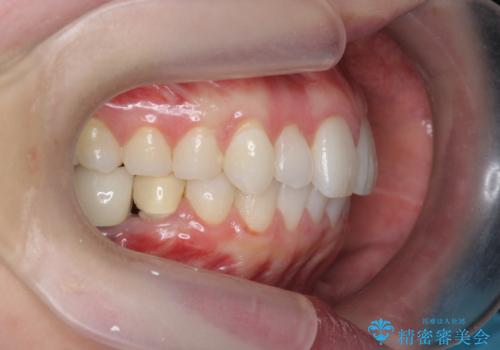

- 前歯のがたつきを主訴に来院。

前歯が引っ込んでいると、そこが影になり大変目立ちます。

矯正治療で大きく見た目を改善することが可能です。